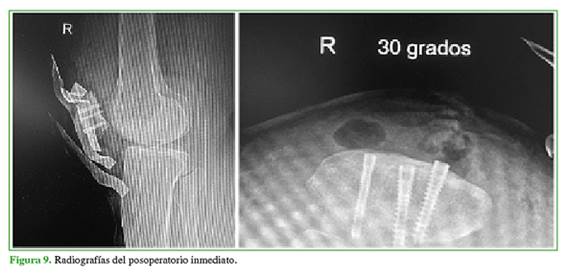

Mujer de 33 años, con dolor crónico de origen rotulofemoral derecho desde 2015, sin mejoría tras la rehabilitación. En 2011, había sido sometida a una condroplastia artroscópica bilateral de rodilla, sin mejoría del dolor. En 2015, se le realizó una viscosuplementación con Dropyal®, tres dosis, pero el cuadro clínico no mejoró. En octubre de 2018, se realizó una resonancia magnética de rodilla que mostró una lesión condral grado III-IV de la rótula (Figura 8). El 13 de junio de 2018 se efectuó un aloinjerto fresco de rótula (Figura 9). En el posoperatorio, presentaba limitación para la flexión, por lo que se realizó una liberación artroscópica de adherencias, y se logró un arco de movilidad de 0° a 125°, sin dolor ni derrame articular, arcos de movilidad activos de 0° a 100°. En la radiografía (Figura 10) y la tomografía computarizada de rótula (noviembre de 2018), se observó la incorporación del injerto.